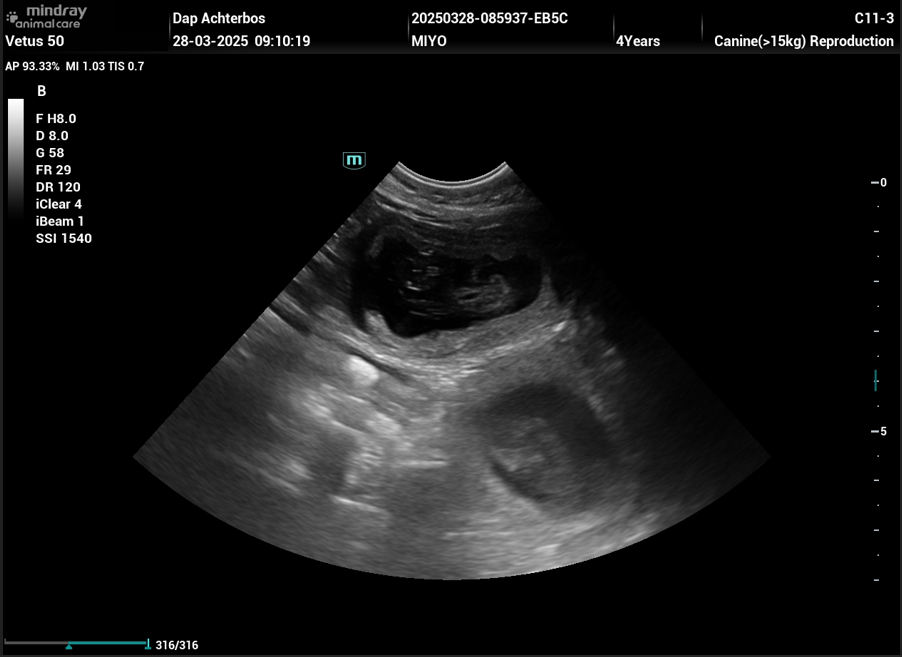

De echo is ondertussen gemaakt op vrijdag 28 maart, en heeft bevestigd dat ze drachtig is, er waren meerdere ‘kloppende hartjes’ te zien op de echo volgens de dierenarts ( zie echo hieronder ).

Uit ervaring weten we dat we enkel kunnen zien of ze drachtig is, maar niet van hoeveel pups exact, daar het hier enkel ‘vruchtjes’ betreft, die kunnen geteld worden. Zelfs voor een ervaren dierenarts is dit zeer moeilijk, daar de hond beweegt tijdens de echo.